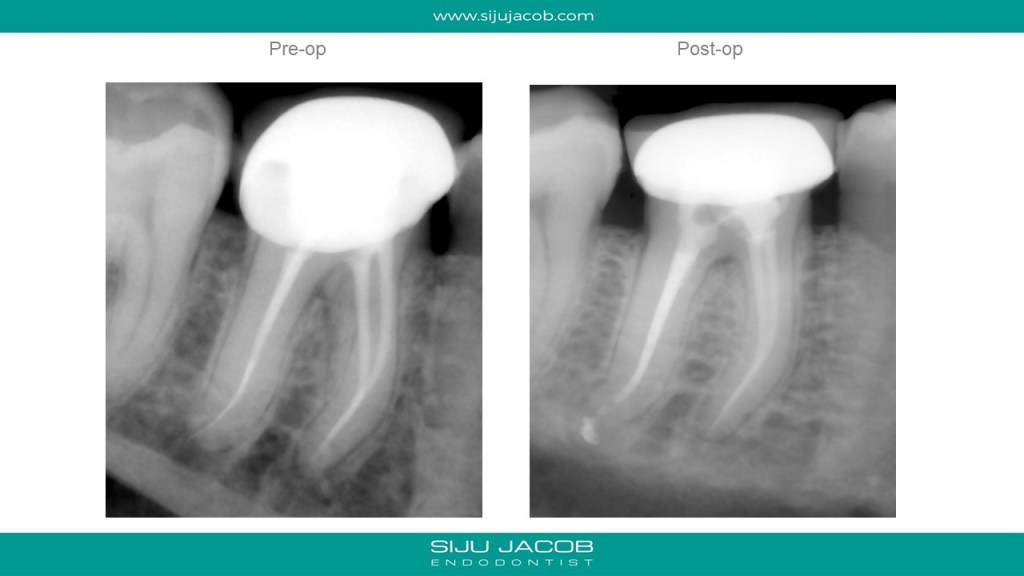

This patient had Endo and crown done a few months ago. While doing the endo, the previous clinician had informed him that she had fractured an instrument and that she couldn’t remove it because it had gone slightly beyond the apex. The mesial canals seemed well-filled. So, I Re-treated only the Distal. Fortunately, the distal canal was ovoid with plenty of access and visualization all the way to the apex. I was able to retrieve the instrument by braiding two H-files on either side of the fragment.